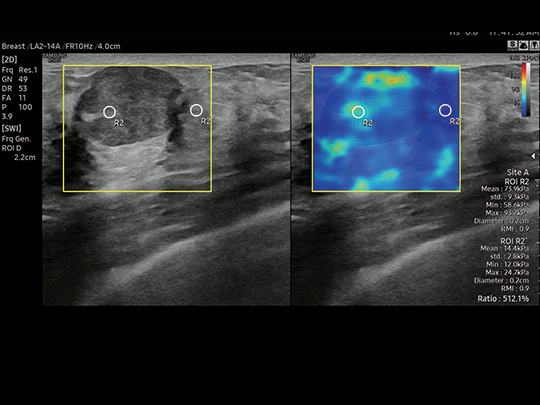

LA2-14A

- Small parts, vascular, musculoskeletal, abdomen